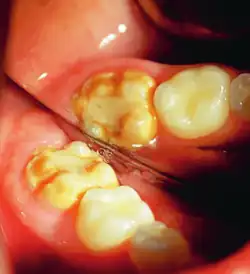

It occurs as a result of severe hypomineralization of the enamel as the enamel appears intact in the initial stages but gradually chips and fractures after the tooth erupts due to the weakened mineral content hence, leading to the formation of rough surfaces and cavities which makes the tooth highly vulnerable to undergo wear, decay and sensitivity.[26] Notably, the post-eruptive breakdown is linked to severe forms of hypomineralization like molar incisor hypomineralization (MIH).[27]

MIH is a specific pattern for which first permanent molars and permanent incisors are affected with the presence of demarcated opacities on the teeth with variations in color from white to yellow and brown.[28] Besides, the enamel which is affected becomes weaker and hence the teeth becomes highly sensitive and likely to undergo post-eruptive breakdown. Notably, the severity of MIH varies among individuals as some experience minimal discomfort and others require extensive dental treatment. Despite MIH remaining idiopathic, it is linked to systemic factors like childhood illnesses, antibiotic use, and nutritional stress during early tooth development.[29]

Enamel hypocalcification is characterized by visible defects in the enamel, often manifesting as white spot lesions or brown discolorations.[35] In cases such as dental fluorosis, this may include mottled patterns on the enamel surface which vary in appearance and extent based on the severity of the condition.[36] In advanced cases, the mottled appearance of the enamel can expose the underlying dentin, creating an uneven and sometimes porous surface. Though the matrix of the enamel initially forms to a typical thickness, the mineralization or calcification process is incomplete or deficient, leading to softer and structurally compromised enamel.[35]

This compromised enamel is more susceptible to staining due to its rougher surface texture and increased permeability, which allows pigments and external elements to penetrate more easily. The weakened enamel may begin to wear away, especially on the occlusal surfaces of the molars, where mechanical forces are most intense. In some individuals affected by severe enamel hypocalcification, the structural deficiencies also contribute to anterior open bite where the upper and lower front teeth do not meet when biting down. This malocclusion can further complicate both functional and aesthetic aspects of the dentition.[37]